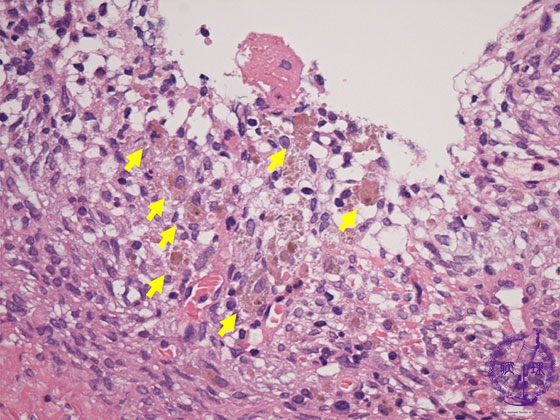

Histology (HE stain, high power): Endometrial stromal tissue and numerous hemosiderin-laden macrophages (yellow arrow) in the cyst wall.